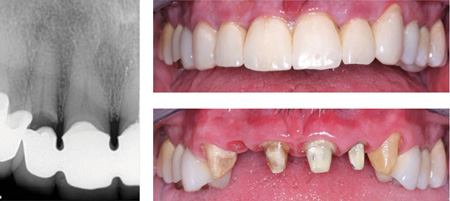

This treatment alternative has been used for nearly 60 years. The first generation had numerous challenges, and several years passed before the technique was accepted by the profession over the then-popular gold alloy full and partial crowns. The refined current generation has been used extensively with improvements and modifications since the late 1950s. Millions of restorations have been placed with a commendable service record (figures 1 and 2).

Figure 1: Failing splinted anterior restorations. Socket grafted with adequate gingival contour created. Grossly overprepared teeth due to repeated treatment.

Figure 2: A comparison of PFM with all-ceramic restorations. Base your own decisions on both history and the research on all-ceramic restorations as summarized in the state-of-the-art information in this article.